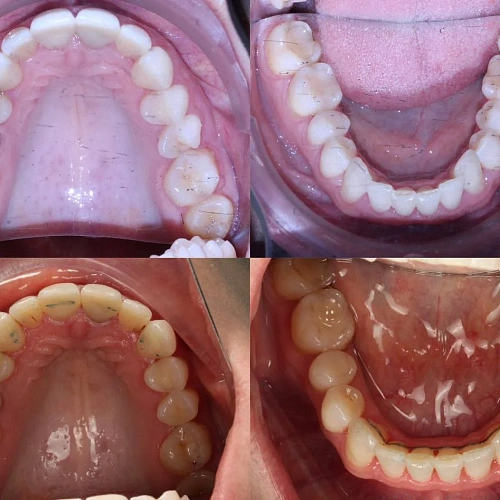

Лечение заняло 20 месяцев (июнь 2024 — февраль 2026). Понадобились два дополнительных набора: 26 и 7 кап — итого 64 капы. Несмотря на дозаказы, лечение уложилось в нормальный срок.

Зубы выровнены, скученность устранена, прикус исправлен, линия смыкания нормализована. Ретейнер установлен на нижнюю челюсть. На верхней ретейнер не ставили — на передних зубах коронки, вместо этого изготовлены ретенционные капы на обе челюсти. Пациентка направлена к ортопеду для замены коронок.

Решение: Поставили элайнеры Click на обе челюсти. Основной набор — 31 капа, плюс два дозаказа: 26 и 7 кап, итого 64. При этом лечение уложилось в 20 месяцев — быстро для такого объёма работы. Расширили дуги, убрали скученность, исправили прикус, выровняли линию смыкания. Ретейнер поставили только на нижнюю челюсть. На верхней от ретейнера отказались сознательно — на передних зубах коронки, и проволока там не ляжет корректно. Вместо этого изготовили ретенционные капы на обе челюсти. Ортопедию — замену старых коронок — пациентка будет проходить у себя в городе.

Непростой случай: II класс, сужение, скученность, деформация кривой Шпее и металлокерамические коронки на 11 и 21. Коронки ограничивают варианты ретенции — на верхней челюсти вместо ретейнера используем капы. Это осознанное решение, принятое совместно с пациенткой. 64 капы за 20 месяцев — хороший темп для такого объёма. Основной набор сделал базу, дозаказы довели до нормы.